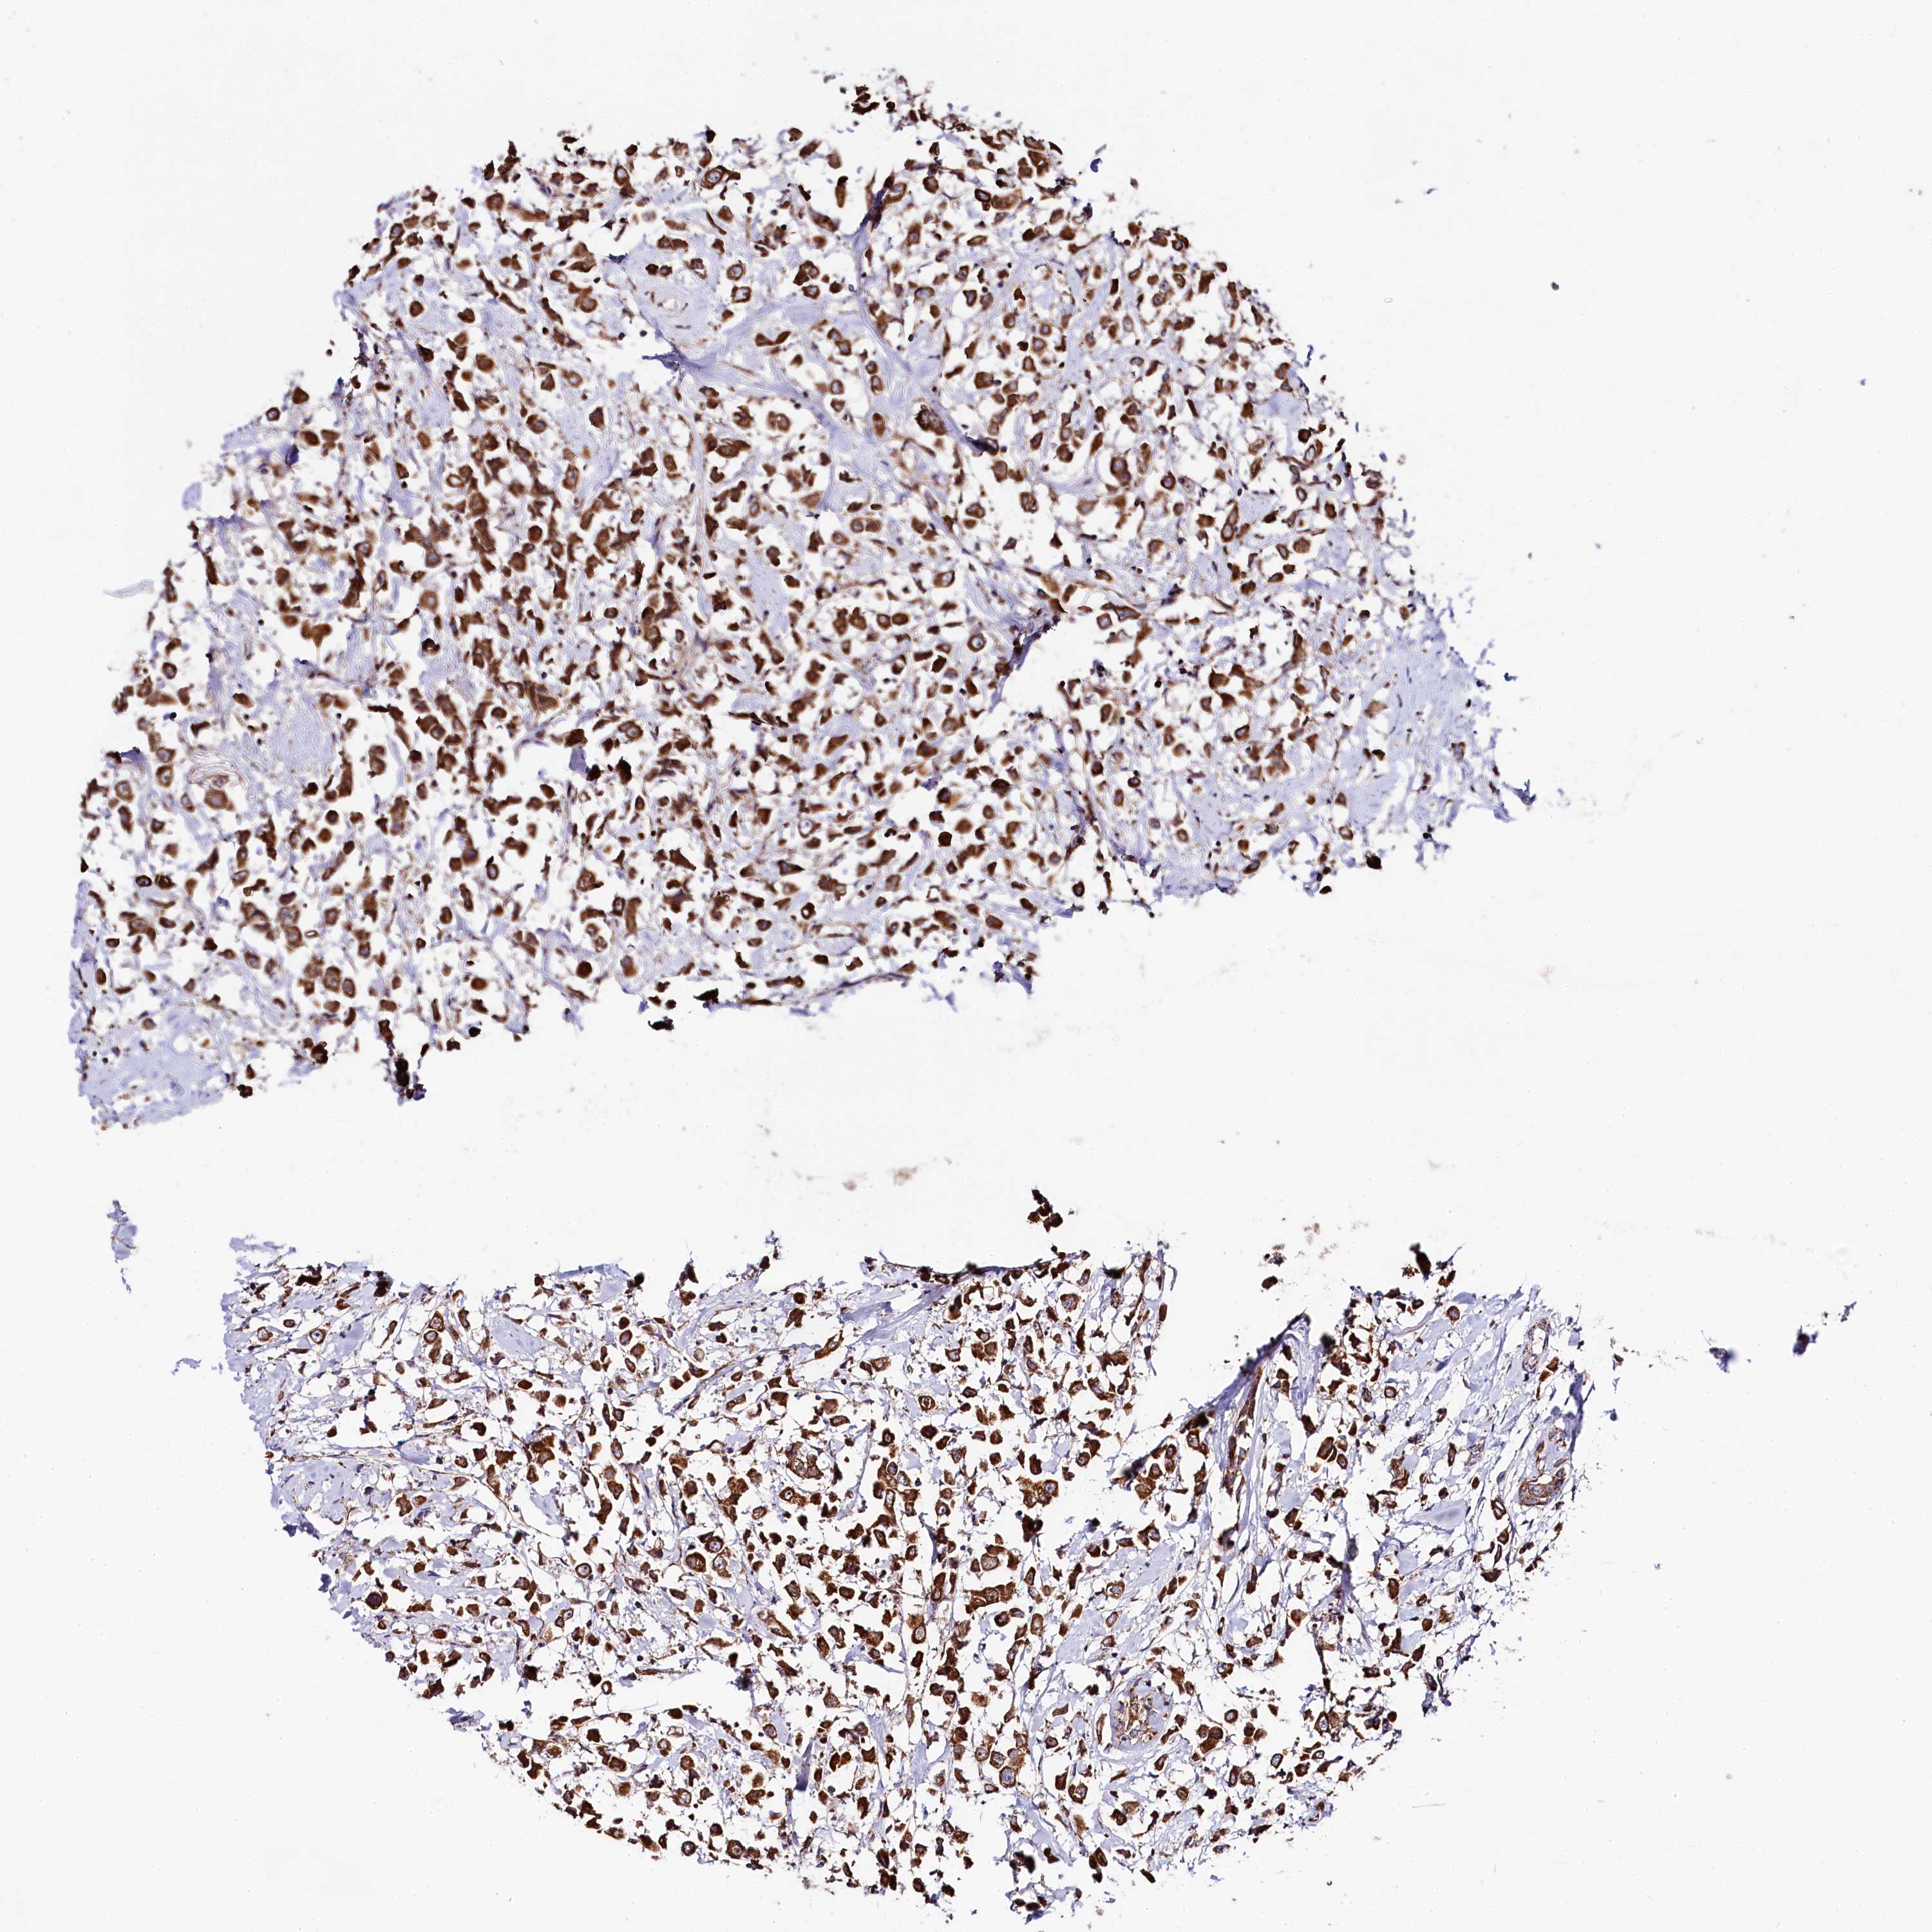

CANCER BREAST CANCER Show tissue menu

BRCA TCGA BRCA VALIDATION PROTEIN EXPRESSION